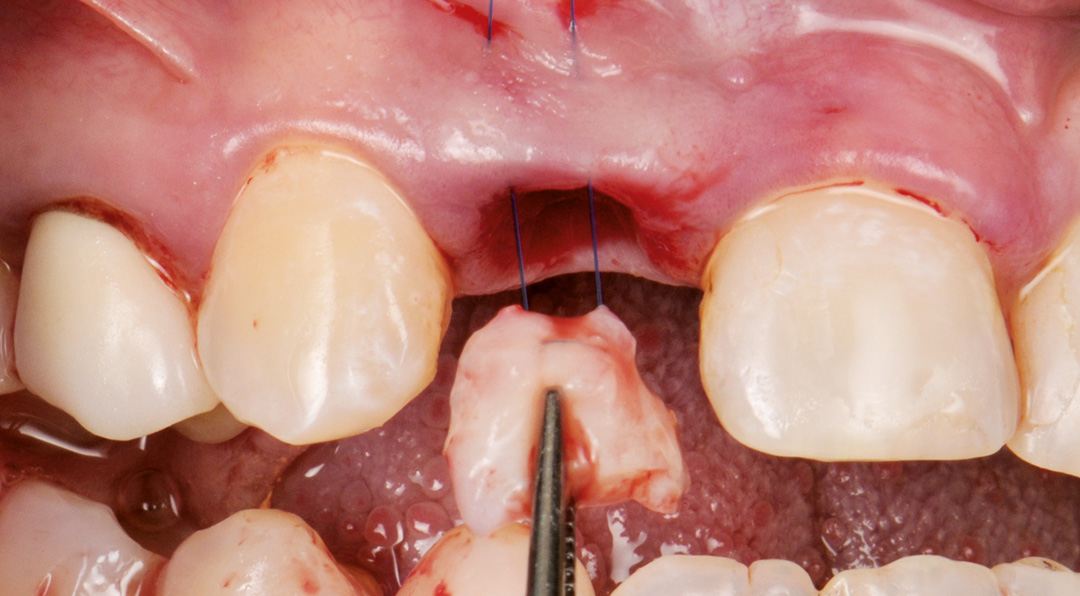

A minimally invasive extraction was performed using the Benex® system to preserve the thin buccal bone. A 3.3 x 11 mm CONELOG PROGRESSIVE-LINE implant was placed using a fully guided protocol. Despite the narrow implant diameter, a torque of 20 Ncm was achieved, facilitated by good palatal bone availability, under-preparation of the osteotomy and the macro design of the implant. The peri-implant gap was grafted with MinerOss X, chosen for its slow resorption profile and volume-stabilising characteristics. A connective tissue graft was harvested from the tuberosity by performing a distal wedge in the region of tooth 1.8. The graft was secured in a buccal pouch using a horizontal mattress suture with 6-0 polypropylene to support the emergence profile and soft tissue volume. A customised healing abutment was placed to seal the socket and guide soft tissue healing. A provisional resin-bonded restoration was applied out of occlusion.